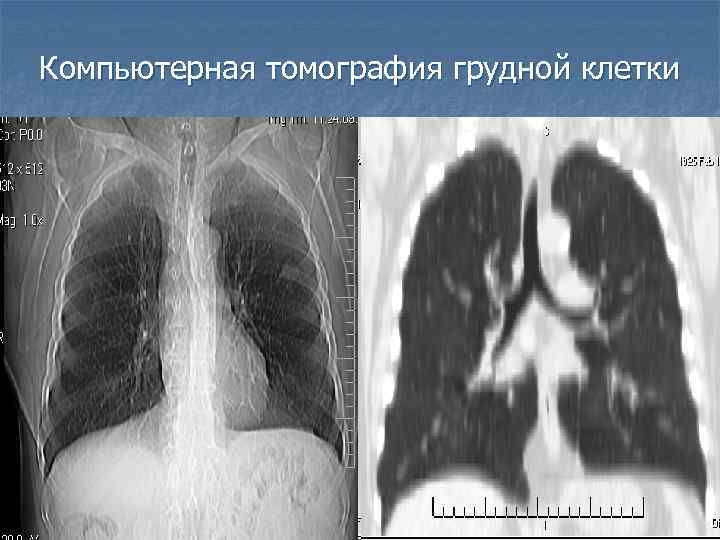

Компьютерная томография грудной клетки